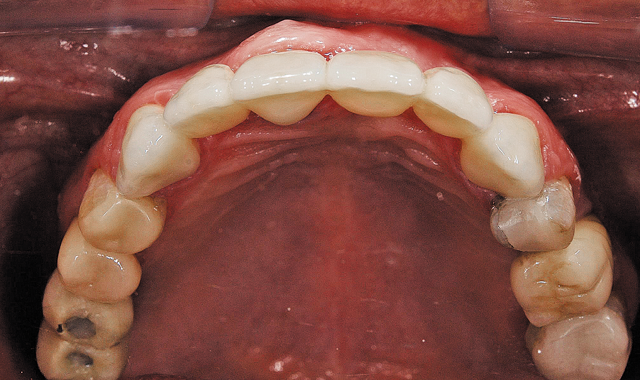

Fig. 7 Oclusal view from provisional bridge, chairside made

02 The doctor first created a four-unit anterior bridge chairside for the patient to establish an initial bite (Fig. 2).

The doctor was able to scan the case chairside using the CEREC Omnicam and then sent the scan to my laboratory digitally via the Sirona Connect network. With inLab’s new Software 15 (SW 15), I can now utilize the amazing new biocopy function to perfectly design and replicate the temporary and then send the six-unit case to mill on the inLab MC X5 wet/dry milling unit.